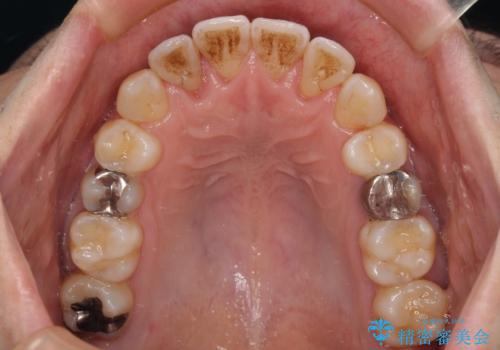

前歯のクロスバイト 目立たないワイヤー装置で矯正治療

舌の突出癖の影響か、下顎前歯がなかなか整わず、治療期間は予定よりも長期間となりました。

舌突出癖改善のトレーニングの重要性を認識することとなりました。